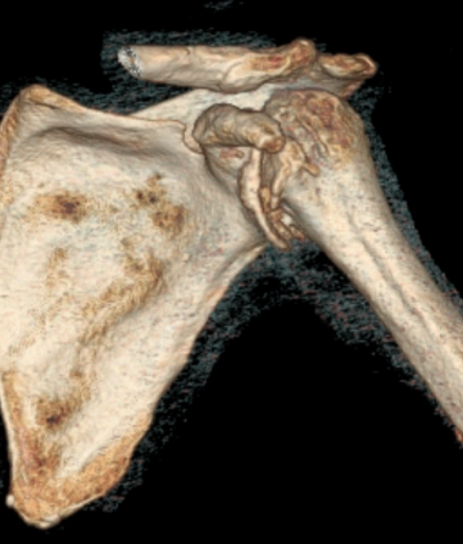

For fracture and revision treatment

The system offers a set of modular Proximal Bodies in several sizes and heights to be paired with a broad range of Modular Stems, available in different diameters and lengths as well as different surface and coating options for cemented and cementless fixation.

The Proximal Bodies’ spiked surface, together with m-l and a-p holes for suture fixation, allow for stable and physiologic tuberosities reattachment. The modular concept of the fracture components supports the surgeon in achieving adequate joint restoration even in cases with poor anatomical landmarks.1